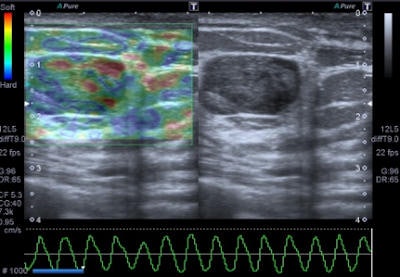

A 47-year-old woman with a small breast lump. Baseline ultrasound shows a hypoisoechoic nodule with regular and well-defined margins. Elastography demonstrates a pattern 2 according to the Ueno-Itoh classification with prevalent elasticity, as a predominance of green, with few, if any, blue and red spots inside. Strain ratio, measured by placing two different regions of interest (placed in normal breast tissue and within the nodule), was 0.36. Gross pathology confirmed a benign fibroadenoma. All images courtesy of Dr. Paolo Ricci.

Benign lesions are described at elastography as lesions with a low color map score (score 1-2), while the best cut-off point for discriminating benign from malignant masses falling at the 3-4 boundary of color map classification, according to the Ueno-Itoh score system. Cysts often appear as hard and low deformable lesions, commonly represented with a blue pattern at the color map and with a high strain ratio because of their low compressibility.

The elastographic properties of fibroadenomas are controversial, because some studies report a substantial difference of fibrotic components than surrounding parenchyma, while other authors describe fibroadenomas as difficult to evaluate by color map because of similar elasticity to the breast gland, the authors noted. Strain ratio range reported by most authors for this specific type of lesion is around 2.1 ± 0.8. Fibroadenomas with larger fibrotic component and poor cellularity can have a suspicious color map, but in all cases the strain ratio is lower than malignant forms, they added.